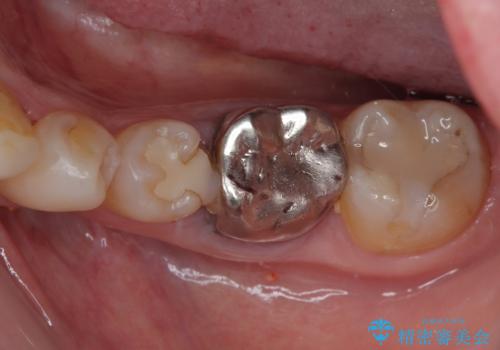

他にも銀歯や欠損となっている歯に対しての治療も希望されたため、補綴治療を行うこととしました。

インプラント治療をきっかけに、銀歯を全てセラミックに替えていきました。